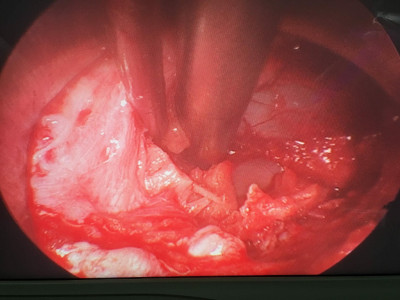

Artroplastía lumbar y prótesis de columna

Envíado por Dr. Hugo Enrique Castro Cordero